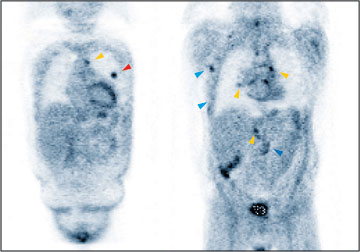

Dieser Patient mit Lymphknotenkrebs befindet sich in einem weitfortgeschrittenen Krankheitsstadium. Befallen sind

Lunge( ), Lymphknoten in Brust- ( ) und Bauchhöhle ( ) und Rippen im Bereich des Brustkorbes ( ). |